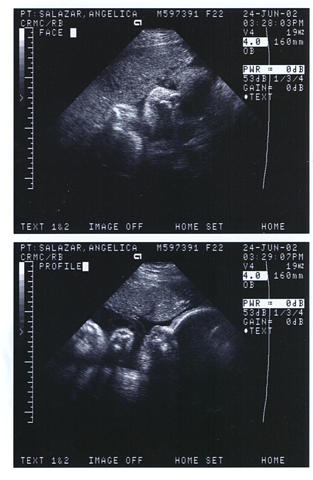

Aqui van

mis primeras fotitos... que

las disfruten...